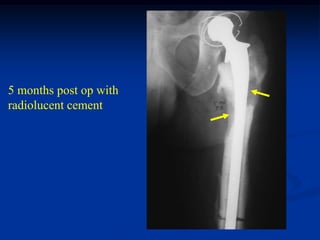

5 months post op with

radiolucent cement